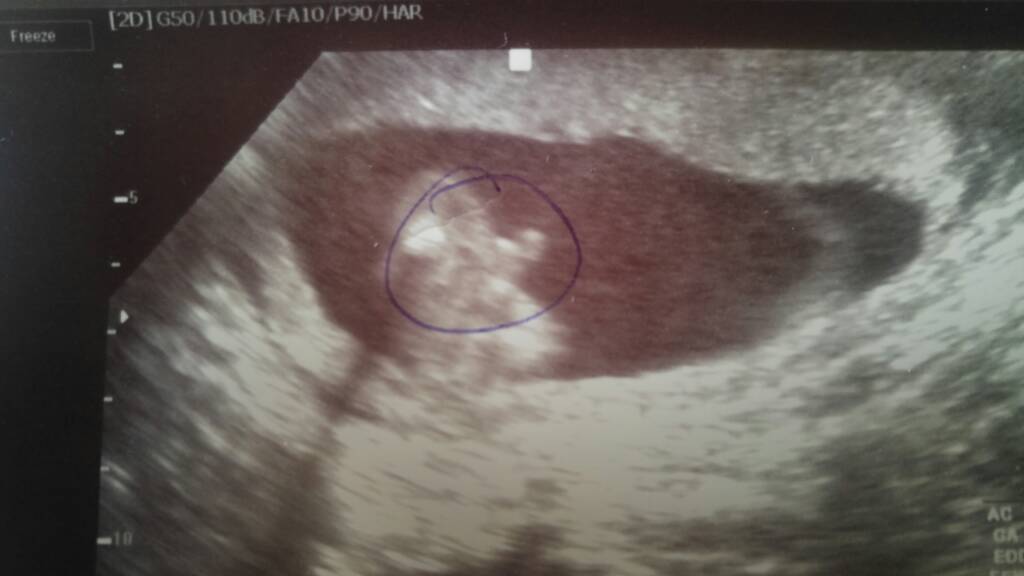

I na 100% Michałek [emoji1][emoji1][emoji1]Zobacz załącznik 838442